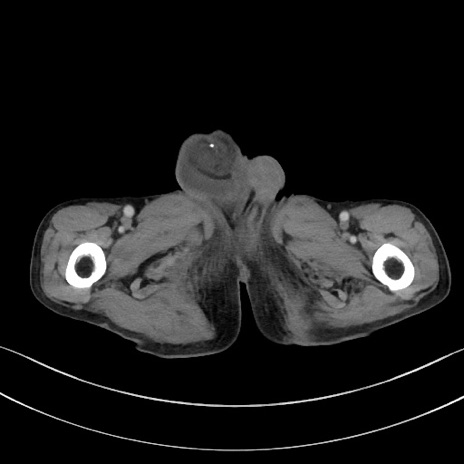

症例3(横断像)

【症例】 70歳代男性

【主訴】右鼠径部腫瘤、疼痛

【現病歴】本日朝より上記主訴あり、受診。

【既往歴】膀胱癌にて膀胱全摘、両側尿管皮膚瘻

【データ】WBC 5600、CRP 0.56